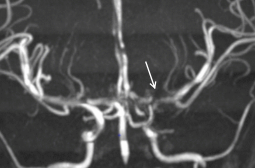

Cerveau

- AVCs ischémiques (200x risque)

- Troubles perfusionnels ++

- Sténoses vasculaires

- Territoires jonctionnels (Carotide++)

- Moya-Moyas